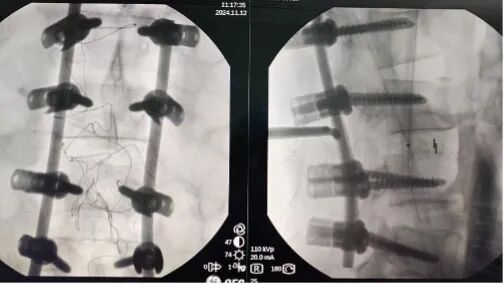

??术后X线片、CT